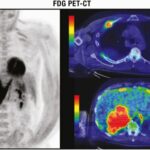

Tomografía por emisión de positrones (PET)

Es una modalidad de medicina nuclear que proporciona imágenes tomográficas cuantitativas después de la inyección intravenosa de un radiotrazador emisor de radiación beta más (positrón) (18-flúor) utilizado para etiquetar la 2-desoxi-D-glucosa que renderiza Fluoro-Desoxiglucosa ([18F]FDG). Tanto la glucosa como la desoxiglucosa entran en las células a través de transportadores de glucosa transmembrana y se someten a fosforilación, pero mientras que la glucosa sufre una mayor descomposición enzimática, la desoxiglucosa queda atrapada en los compartimentos intracelulares. Las células cancerosas tienen una mayor necesidad de glucosa y, por lo tanto, ingieren más glucosa y desoxiglucosa que las células normales. Sin embargo, la FDG no es un marcador específico para las células cancerosas, sino solo un marcador para aumentar el metabolismo de la glucosa. Por lo tanto, la absorción también puede aumentar en las células con un mayor requerimiento de energía debido a condiciones distintas del cáncer, por ejemplo, la infección activa.

La medición cuantitativa de las concentraciones de [18F]FDG dentro de los tejidos proporciona el índice de medición clínica más utilizado, el valor de captación estándar (SUV), que compara la intensidad de la captación de 18F en la lesión suprarrenal con la captación promedio de todo el cuerpo. Los valores estándar de absorción se han utilizado para diferenciar entre lesiones suprarrenales benignas y malignas. El FDG-PET por sí solo tiene una alta sensibilidad para la detección de cambios metabólicos, pero su resolución espacial para la localización anatómica es pobre. La solución es una fusión de hardware entre PET y CT (PET/CT) que permite la adquisición simultánea de datos de PET y CT. En la práctica clínica, esto implica inyectar a los pacientes con trazadores de FDG al menos una hora antes del inicio de la PET/CT combinada. Además de su potencial de diagnóstico para discriminar entre lesiones suprarrenales benignas y malignas, la FDG-PET/CT puede ayudar, en caso de sospecha de carcinoma adrenocortical o feocromocitoma, a identificar metástasis y, en caso de sospecha de metástasis suprarrenal, a detectar el tumor primario.

Tiene una alta precisión diagnóstica para la caracterización de las masas suprarrenales con una sensibilidad agrupada del 91% y una especificidad del 91% en un metaanálisis reciente de 29 estudios en los que participaron 2421 pacientes.(25) Esta técnica es más cara y está menos disponible que la tomografía computarizada y la resonancia magnética, pero puede ayudar a discriminar la enfermedad metastásica de las masas benignas en pacientes con malignidad conocida(26) (Figura 3). Una limitación es que las lesiones suprarrenales benignas, particularmente los adenomas funcionales y los feocromocitomas no metastásicos, pueden ser FDG positivos.